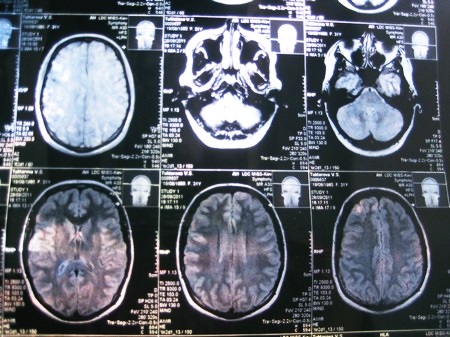

Рентгенография черепной коробки требуется для определения уровня нарушения развития костей, которые нередко сопровождают синдром Арнольда Киари. КТ, как и МСКТ головного мозга, несмотря на достаточно хорошую визуализацию костных структур краниовертебрального перехода, не дают возможности неврологам полностью определить состояние мягких образований в задней ямке черепа.

В связи с этим в последнее время наиболее часто применяется МРТ (магнитно-резонансная томография) – единственный простой и достоверный способ диагностики данной аномалии развития головного и спинного мозга. Поскольку для ее проведения необходима полная обездвиженность человека, то для обследования маленьких детей вводят в состояние так называемого медикаментозного сна.

Помимо МРТ головного мозга, неврологи могут дать направление на проведение МРТ грудного и шейного отделов позвоночника. Показанием для этого является подозрение на параллельное развитие сирингомиелических кист либо менингоцеле. Еще одним важным преимуществом данной методики является то, что она помогает обнаружить даже слабо выраженные нарушения в развитии центральной и периферической нервной системы, которые могут сопровождать аномалию Киари.